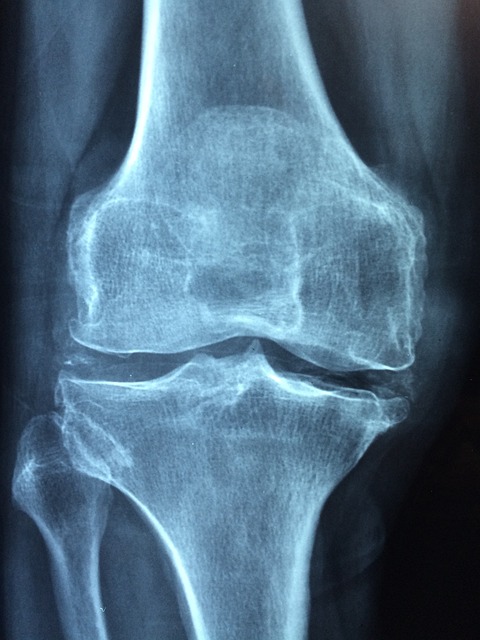

- 뼈 건강 유지

◆ 효과: 비타민 D는 칼슘과 인의 흡수를 촉진하여 골다공증을 예방하고, 뼈의 밀도를 유지하는 데 도움을 줍니다. 특히, 중년 이후에는 골밀도가 감소하기 쉬워 비타민 D의 충분한 섭취가 중요합니다.

◆ 사례: 비타민 D 결핍으로 인해 발생할 수 있는 골연화증, 골다공증 등의 사례를 통해 그 중요성을 강조합니다.